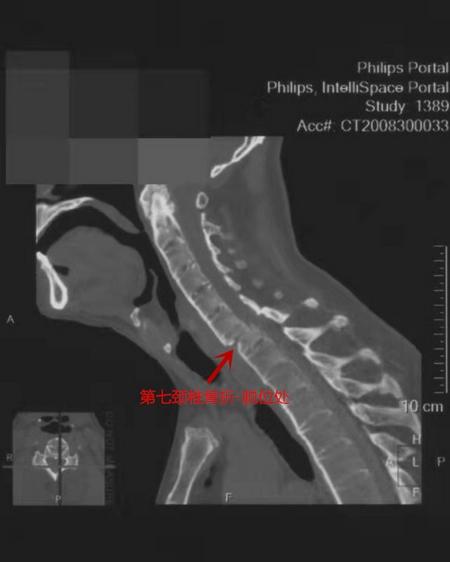

ct检查显示,张先生第七颈椎骨折,脱位,脊髓和神经受压严重.